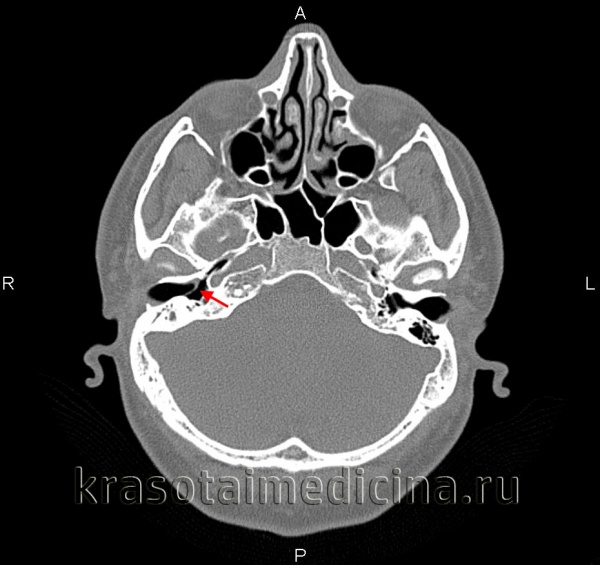

Компьютерная томография височных костей высокого разрешения (КТ) — это высокоинформативный объективный метод диагностики отосклероза. КТ позволяет точно визуализировать структуры височных костей, выявлять расположение, распространённость очагов и активность отосклероза. Также можно выявить очаги как пониженной, так и повышенной плотности.

КТ-сканирование играет важную роль при диагностике перед кохлеарной имплантацией: позволяет оценить состояние связочного аппарата и слуховых косточек, определить объём, тактику и прогноз операции. Диагностическая чувствительность КТ височных костей составляет 80–95 % [3] .

Происходящие при отосклерозе изменения костной ткани капсулы лабиринта иногда определяются по результатам прицельной рентгенографии черепа. Однако более информативным исследованием является КТ черепа, позволяющая визуализировать очаги отосклероза.

КТ височных костей. С обеих сторон диффузное снижение пневматизации ячеек сосцевидного отростка и пирамиды височной кости за счет отосклероза